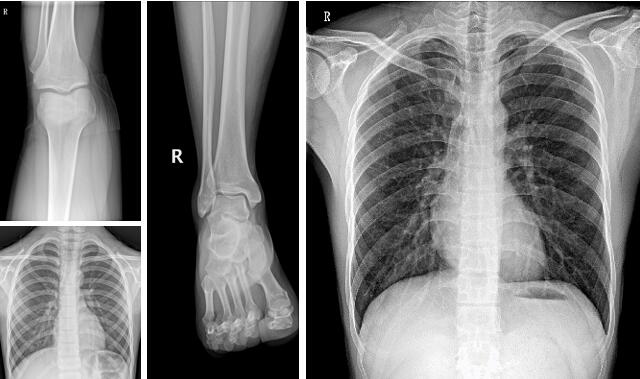

3、骨科。操作方便、工作效率高,可移動dr機-PLX M5320可滿足人體的頭部、四肢、胸腔、脊柱、腰椎、腹部等全身各部位的數(shù)字化攝影的工作需求。

【PLX M5320移動DR臨床圖像】